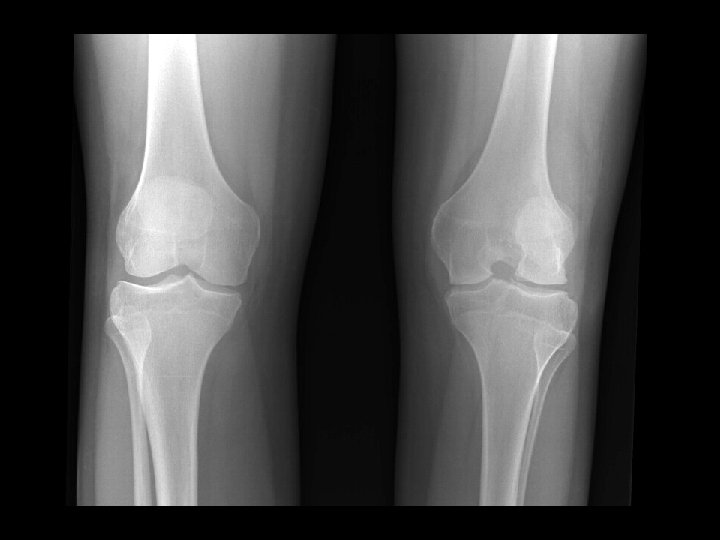

Juvenile Rheumatoid Arthritis • Findings: – Flared metaphyses – Gracile diaphyses – Joint space narrowing – Abnormal patellae • ddx: – NONE! – This is an Aunt Minnie!

Inflammatory Arthritis • • Findings: – Severe joint space narrowing – Sub-chondral cystic changes and sclerosis – No significant osteophyte formation ddx: – Post-infectious